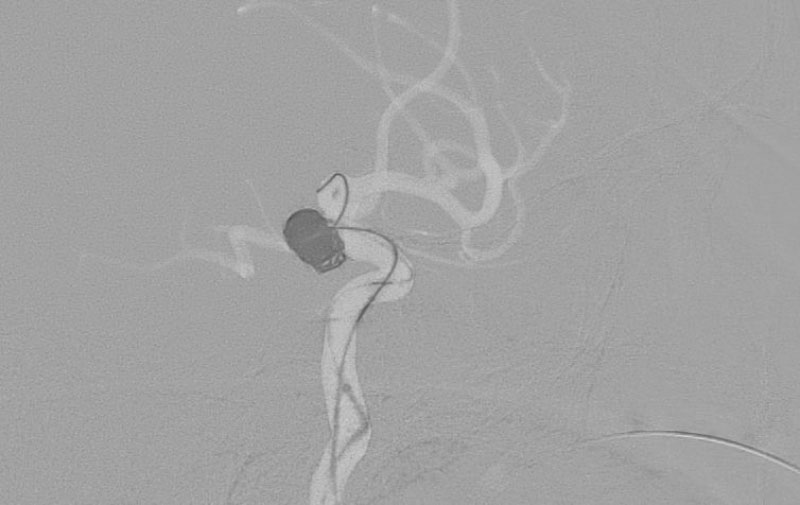

くも膜下出血

左中大脳動脈瘤破裂

40代

救急外来

No.1596 手術前

No.1596 手術中

No.1596 手術後